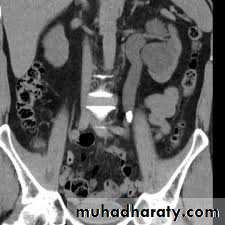

4. Horseshow kidney: fusion of the lower

pole, long axis parallel to the spine, mal-rotationof both kidneys so the pelvis of the kidneys

directed anterior or lateral . Obstruction and

infection are common . Its diagnosis is suggested

by US and confirmed by IVU or CT